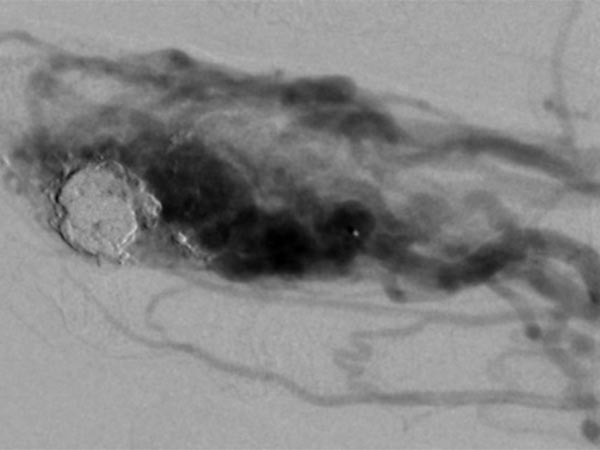

After incomplete transarterial embolization of the AVM 2 years ago, a recurrence of the AVM has appeared. During previous embolization only a part of the AVM was occluded, which actually increases the risk of recurrence. The old radiopaque embolic agent of the previous embolization can be seen centrally in the nidus.

The nidus of the AVM in a magnified target image of the D III in digital subtraction angiography shows significant increase in size compared to the old angiographies (not shown). DSA images after transarterial antegrade puncture of the brachial artery with hypervascularized AVM of the middle and distal phalanx.

Angiographic control of the right hand with catheter injection from transarterially via the ulnar artery. Complete devascularization of the AVM nidus. No fast-flow shunts can be angiographically detected. The treated AVM with occluded nidus is thus resectable.